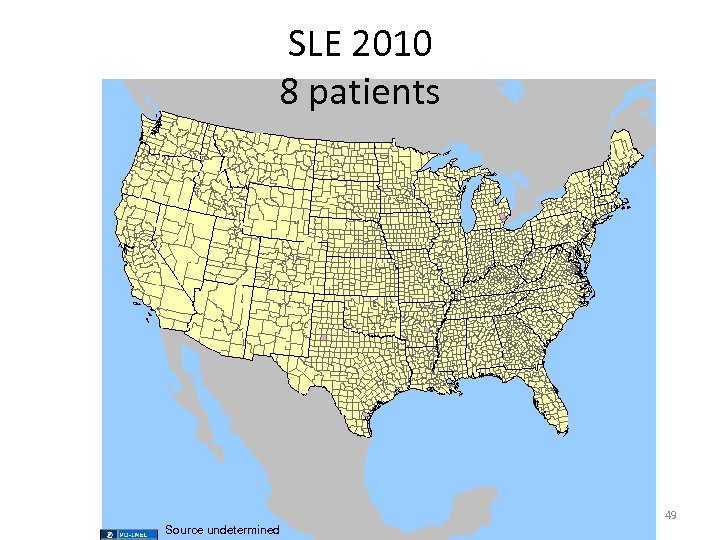

SLE 2010 Source undetermined 48

SLE 2010 8 patients 49 Source undetermined